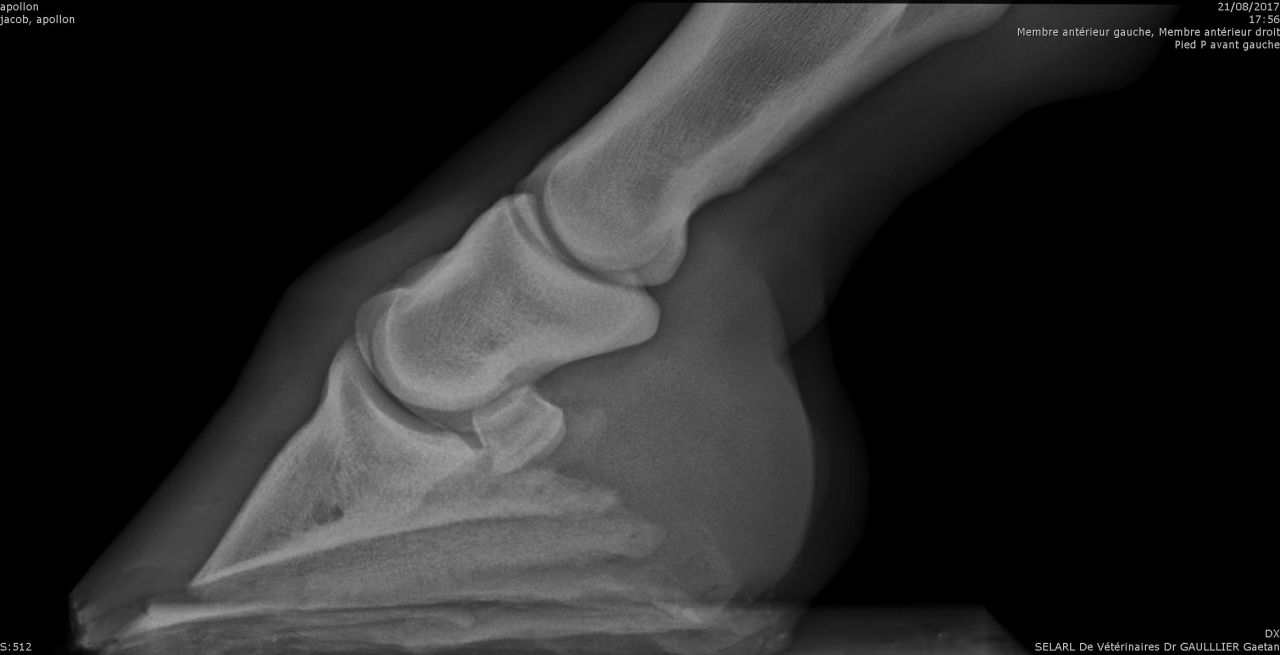

| Dire merci | Alors pour les fers, je ne suis pas une ayatollah du pieds nus, donc je l'ai évoqué avec la véto. Selon elle à ce stade, ça ferait plus de mal que de bien, pour les raisons suivantes : - jument confortable au pré, puisque terrains bien mous en ce moment - difficulté à ferrer vu ce qu'il "reste de pied", elle pense que ça va être un calvaire pour la jument de clouer - si jamais c'est un soucis de vascularisation, ça va plutôt amplifer le soucis Concernant les PHW, justement avec Kaline on était passé à une orthopédie à base de PHW, parce que pas moyen de faire tenir des fers compensés en talon dans la boue. Après ça dépend beaucoup de la locomotion du cheval, mais vu que Cam' n'est pas une foudre de guerre et que même si le pré est boueux on ne s'enfonce pas tant que ça, je suis plutôt confiante. Pour la biotine je veux bien des infos. Moi on m'a souvent dit que ça rendait l'organisme "paresseux" pour en produire lui même, et que si la flore digestive et les apports nutritionnels sont ok y a pas de raison d'avoir de carence ? J'aurais donc plutôt tendance à agir là dessus ? Les radios en spoilers pour celles et ceux que ça intéresse. Message édité le 19/02/18 à 17:18 |